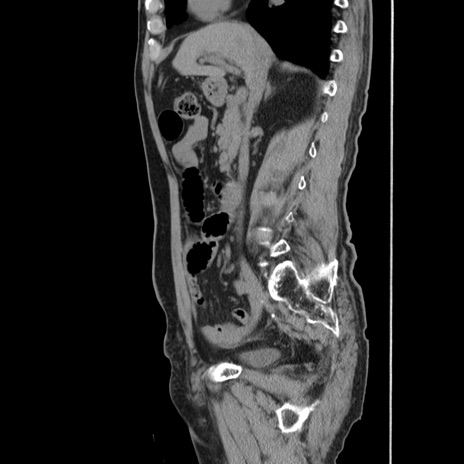

症例24(矢状断像)

【症例】80歳代男性

【主訴】左側腹部痛、嘔吐

【現病歴】本日早朝より左腹部に痛みあり。昼頃嘔吐認めたため、救急要請。

【既往歴】直腸癌(Mile手術)、胆摘

【身体所見】意識清明、BT 35.9℃、BP 221/93mmHg、SpO2 97%(RA) 、腹部:左ストーマ周囲に限局性の腹部膨隆あり。 膨隆部自発痛・圧痛あり・軟。

【データ】WBC 7700、CRP 0.09